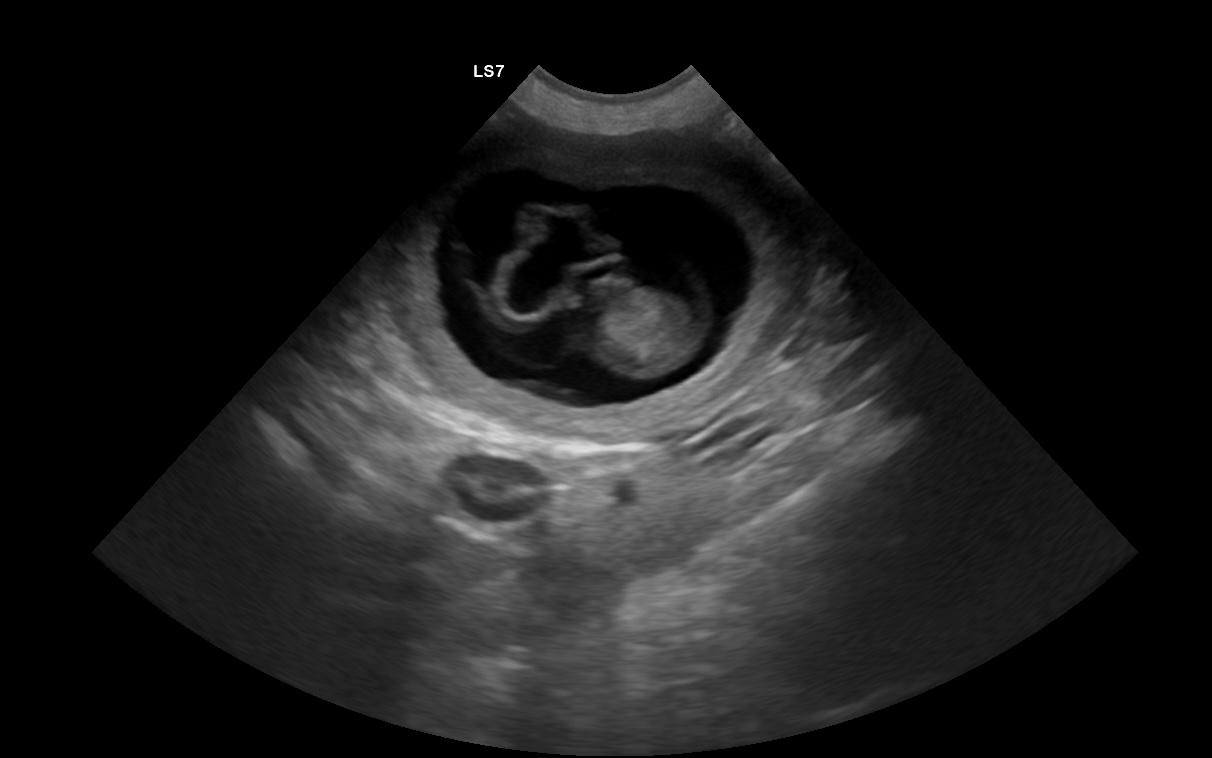

Op 08 oktober 2025 zijn Catoo en Koby ouders geworden van 1 teefje en 2 reutjes.

Uit deze combinatie zijn 3 pups geboren:

-> Daisy Duck v.d. kleine Vlaegelkes

-> Donald Duck v.d. kleine Vlaegelkes

-> Daffy Duck v.d. kleine Vlaegelkes